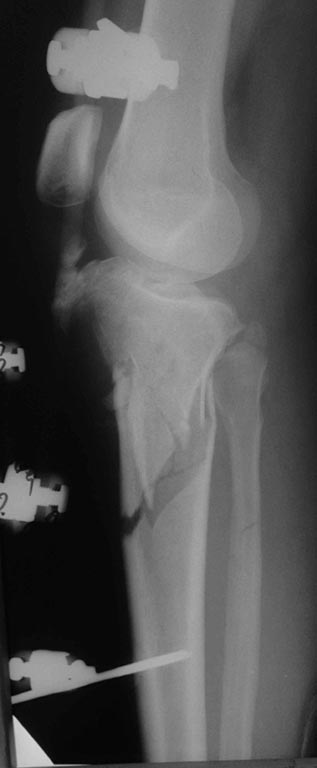

[Ortho] перелом проксимальной тибии + вывих бедра

сегодня только такое